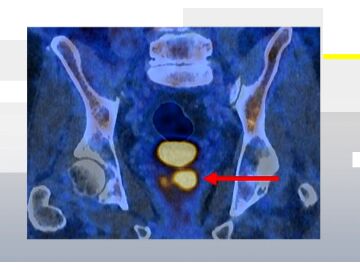

Cáncer próstata Una nueva prueba que hace "brillar" el cáncer de próstata podría evitar la mitad de las biopsias